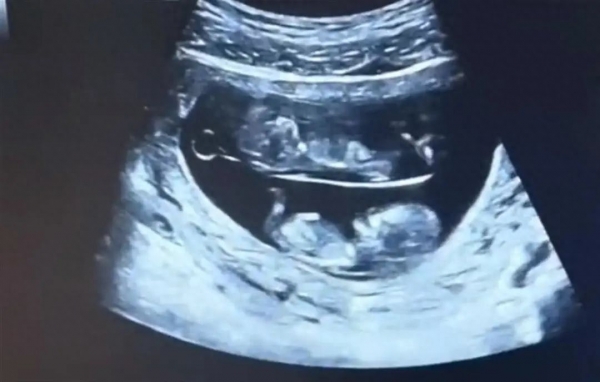

近日,一对还未出生的双胞胎宝宝火爆全网,有网友晒出了他们的B超照,十分有趣。

视频中

两个宝宝在母亲的肚子里

呈上下分布

并且还不停踢动

对此网友评论调侃

"原来双胞胎还有'上下铺'啊!"